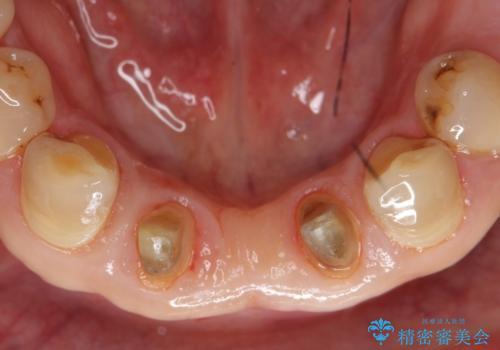

- 前歯の保険のブリッジが欠けてしまっているのを治したいとのことでした。

前装冠が剥がれていて、下の金属が見えてしまっていました。

保険のブリッジは入れてすぐ欠けてしまったのを長年使用していたとのことです。

かみ合わせもきつく、ジルコニアクラウンではセラミックでも欠けてしまいそうでした。

今回は、丈夫な欠けにくいフルジルコニア(ヴェレッツァ)クラウンでブリッジにすることにしました。